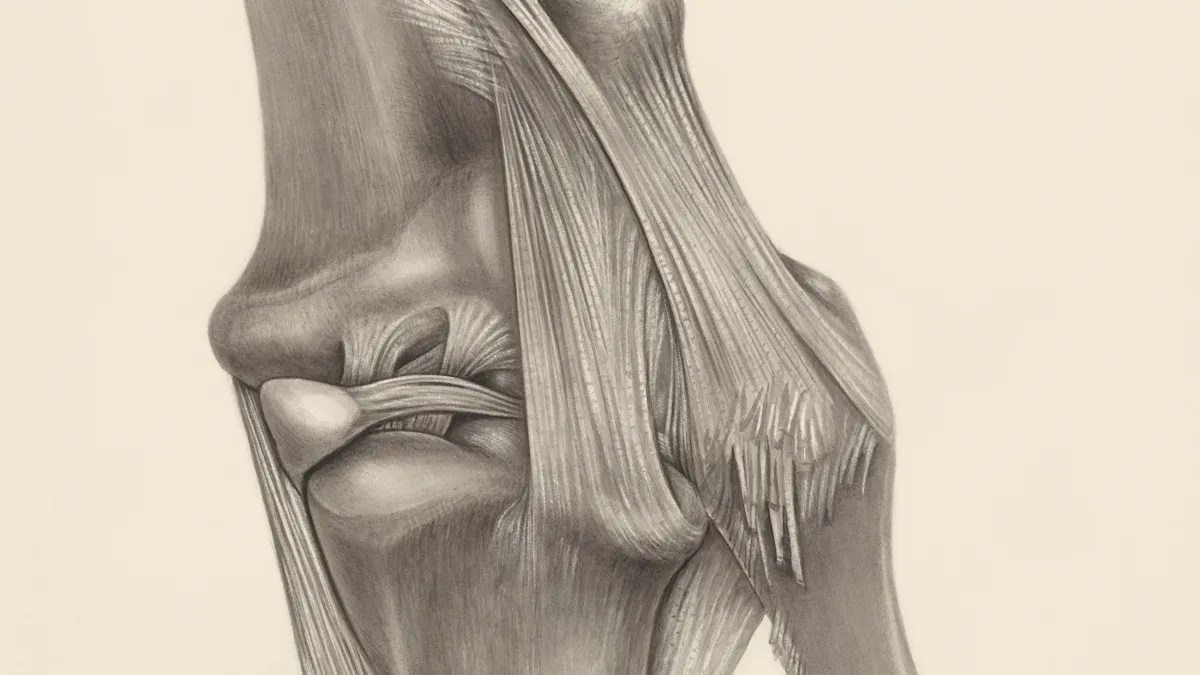

How It Supports Cartilage and Connective Tissue

You want strong joints and lasting mobility. Glucosamine acts as a building block for glycosaminoglycans and proteoglycans, which are vital for cartilage health. Vegetarian glucosamine helps your body synthesize these compounds, supporting cartilage regeneration and joint mobility. Studies show glucosamine supplementation can reverse inflammation in chondrocytes and boost hyaluronic acid production. The table below highlights how vegan glucosamine works:

| Supporting cartilage structure | Maintains joint space and function |

| Reducing inflammation | Eases joint discomfort |

| Improving joint lubrication | Enhances joint mobility |

| Enhancing repair processes | Promotes tissue regeneration |

| Antioxidant protection | Shields joint tissue from damage |